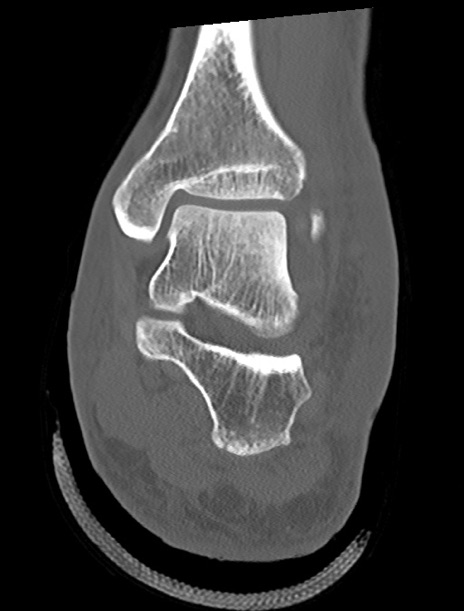

左足関節CT

矢状断像